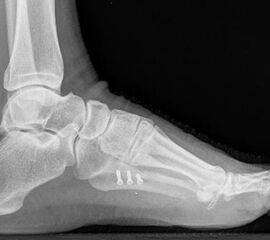

Abb. 12c: Schrägaufnahme nach medial schließender Osteotomie mit Schraubenosteosynthese.

Abb. 12d: Seitliche Aufnahme nach medial schließender Osteotomie mit Schraubenosteosynthese.